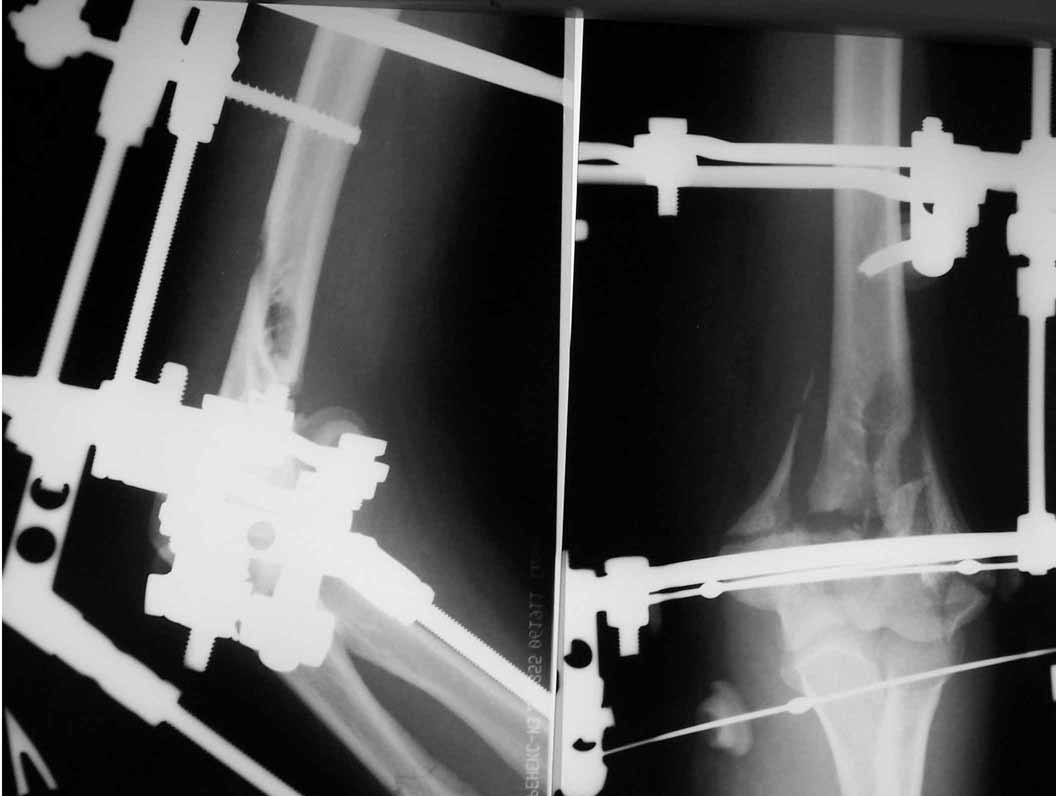

Женщина 42 лет, операция через неделю после перелома.

Д-з - открытый перелом мыщелков со смещзением и локтевой кости

без смещения - падение с лошади.

До операции снимки не очень, тем более в гипсе.

Остеосинтез закрытый (если так можно выразиться), т.е. без

разрезов. Длительность операции - около 1,5 часа со студентом.

6 щелчков ЭОПом.